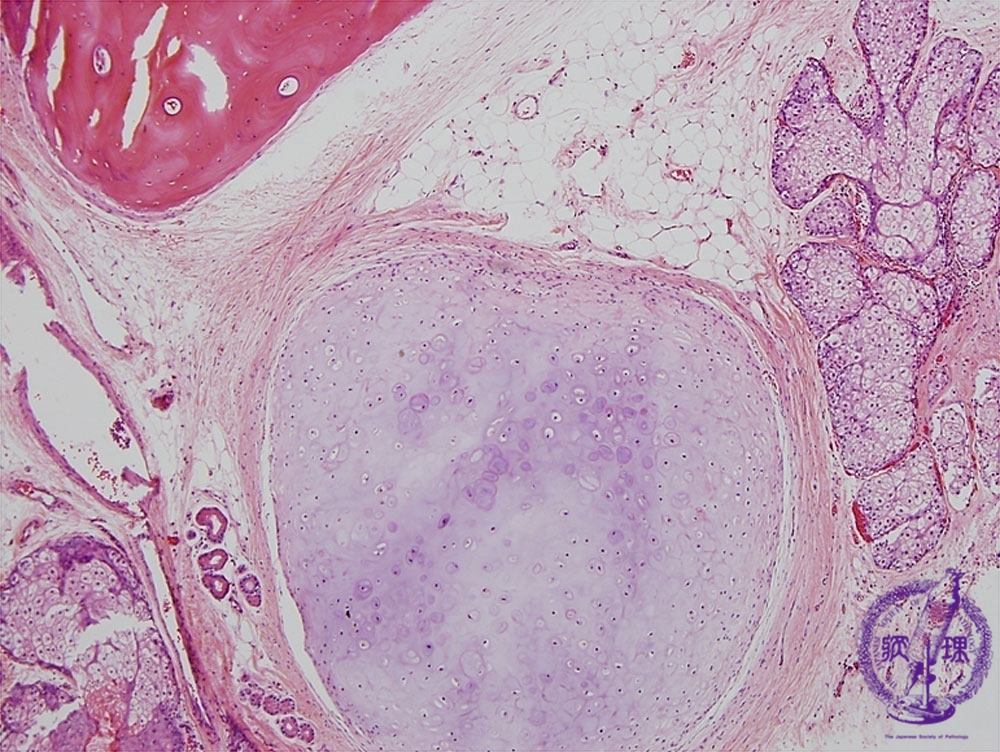

- ★(9)Ovarian teratoma(Mature cystic teratoma)

Histology (HE stain, low power): Mature cystic teratoma. Bone (yellow dotted line), cartilage (blue dotted line), and sebaceous gland (red dotted line).